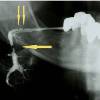

Сиалография – контрастное рентгенологическое исследование слюнных желез и их протоков. В стоматологии проведение сиалографии показано при сиаладенитах, сиаладенозе, сиалолитиазе, опухолях слюнных желез. Всего в Краснодаре найдена 1 клиника, где можно сделать сиалографию.

Сиалография